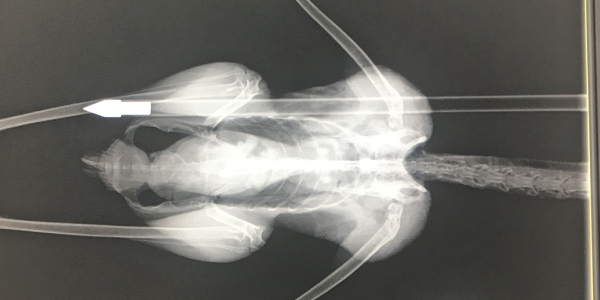

RSPCA Qld is appealing for any information in relation to the shooting of a curlew on the morning of Thursday December 13th. An informant found the bird with an arrow embedded in its side in a park on Woodrose Road Morayfield.

Incredibly the curlew survived and is currently undergoing rehabilitation at Australia Zoo.